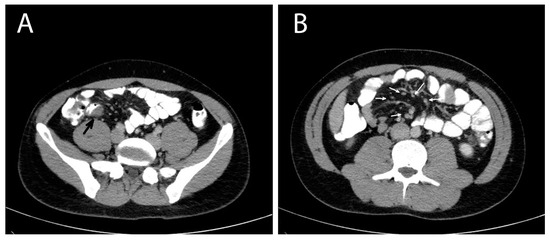

Considering the abovementioned findings, the young age of the patient and the absence of a definitive diagnosis, a diagnostic laparoscopy was performed, revealing a dilated terminal ileum with localized oedema and a firm round nodule of ~1 cm in diameter in the mesenteric border of the distal ileum, about 2 cm from the ileocolic junction. Many enlarged lymph nodes were found along the ileocolic and middle colic vessels and the greater omentum. Another firm nodule was found in the mesocolic border of the descending colon approximately 2 cm in diameter (Figure 2). There were no signs of diffuse peritoneal disease. Neoplasia was suspected and the operation converted to an open laparotomy through which an extended right colectomy and an omentectomy were performed. A side-to-side ileotransverse anastomosis re-established the continuity of the gastrointestinal tract. The nodule of the descending colon was also excised. The patient had an uneventful course and was discharged on postoperative day 13.

Figure 2. Colectomy of a patient with invasive intestinal anisakiosis. Multiple enlarged lymph nodes (arrows) and a lesion in the distal ileum (circle, also shown in Figure 1A) are visible.